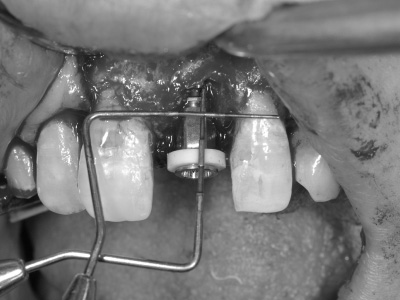

シミュレーションソフトを用いて正しいポジションにインプラントを埋入。

インプラントは骨の中に入るようにできるだけ細いものを使用していますが、それでも骨造成は必要です。

そこで、上顎から切り取ってきた歯茎をインプラント周りに移植し、歯茎に厚みを持たせます。

インプラント周りに骨造成も実施しました。